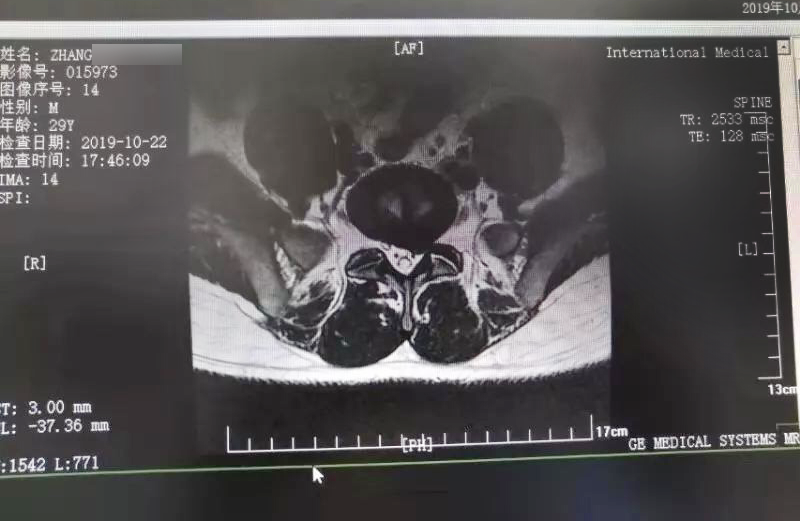

三秦網(wǎng)報道—西安國際醫(yī)學中心骨科醫(yī)院成功完成首例椎間孔鏡手術(shù)

三秦網(wǎng)報道—西安國際醫(yī)學中心骨科醫(yī)院成功完成首例椎間孔鏡手術(shù)。點擊閱讀。